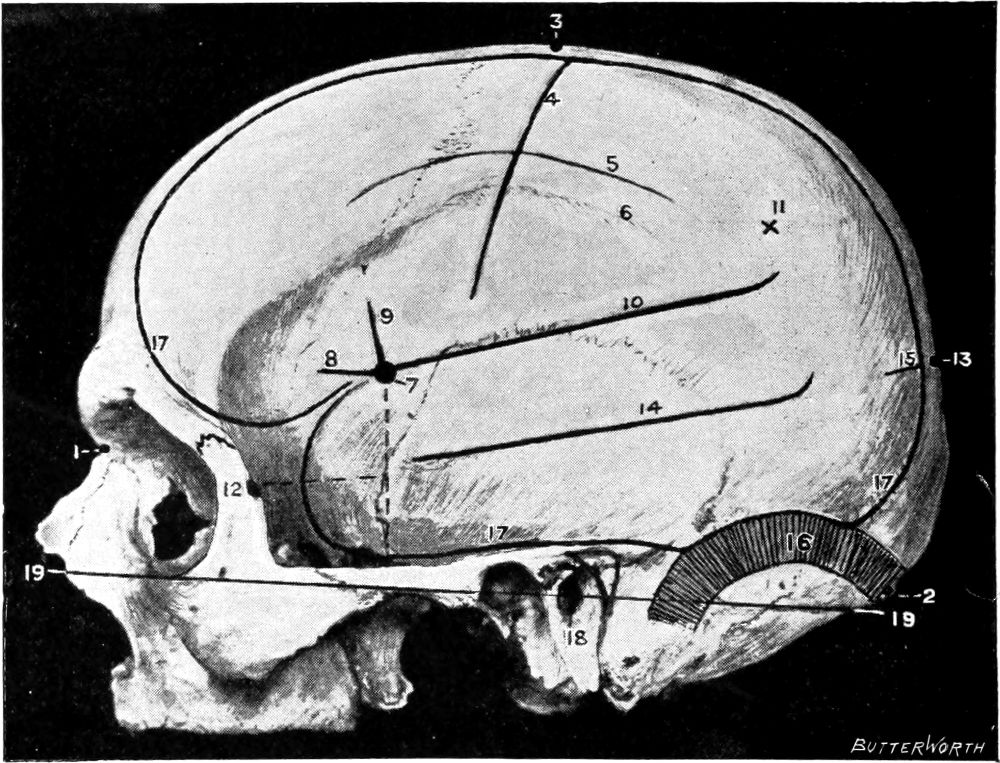

Fig. 1. Cranio-cerebral Topography. 1, The nasion; 2, The inion; 3, The mid-point between nasion and inion; 4, The Rolandic fissure; 5, The superior temporal crest; 6, The inferior temporal crest; 7, The Sylvian point; 8, The anterior horizontal limb of the Sylvian fissure; 9, The vertical limb of the Sylvian fissure; 10, The posterior horizontal limb of the Sylvian fissure; 11, The parietal prominence; 12, The malar tubercle; 13, The lambda; 14, The first temporo-sphenoidal sulcus; 15, The external parieto-occipital sulcus; 16, The lateral sinus; 17, 17, 17, The level of the base of the cerebrum; 18, The external auditory meatus; 19, 19, Reid’s base-line. (Reproduced, by the permission of Mr. H. K. Lewis, from the author’s work on ‘Landmarks and Surface-markings’.)

Larger illustration (top)

Larger illustration (bottom)